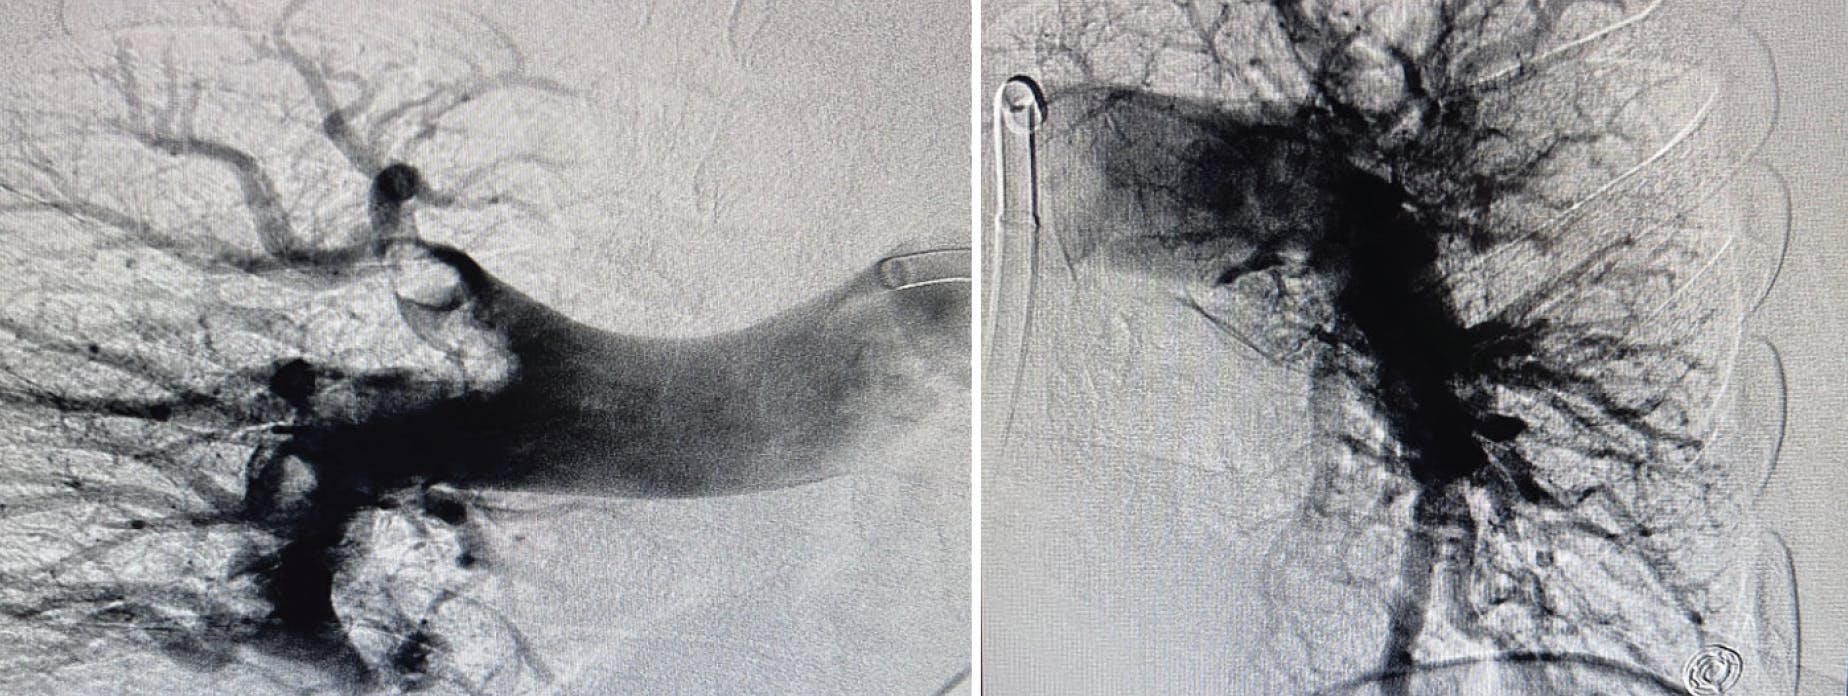

Figure 2. Preprocedural angiograms of the right and left PA.

Figure 3. Postprocedural angiograms of the right and left PA.